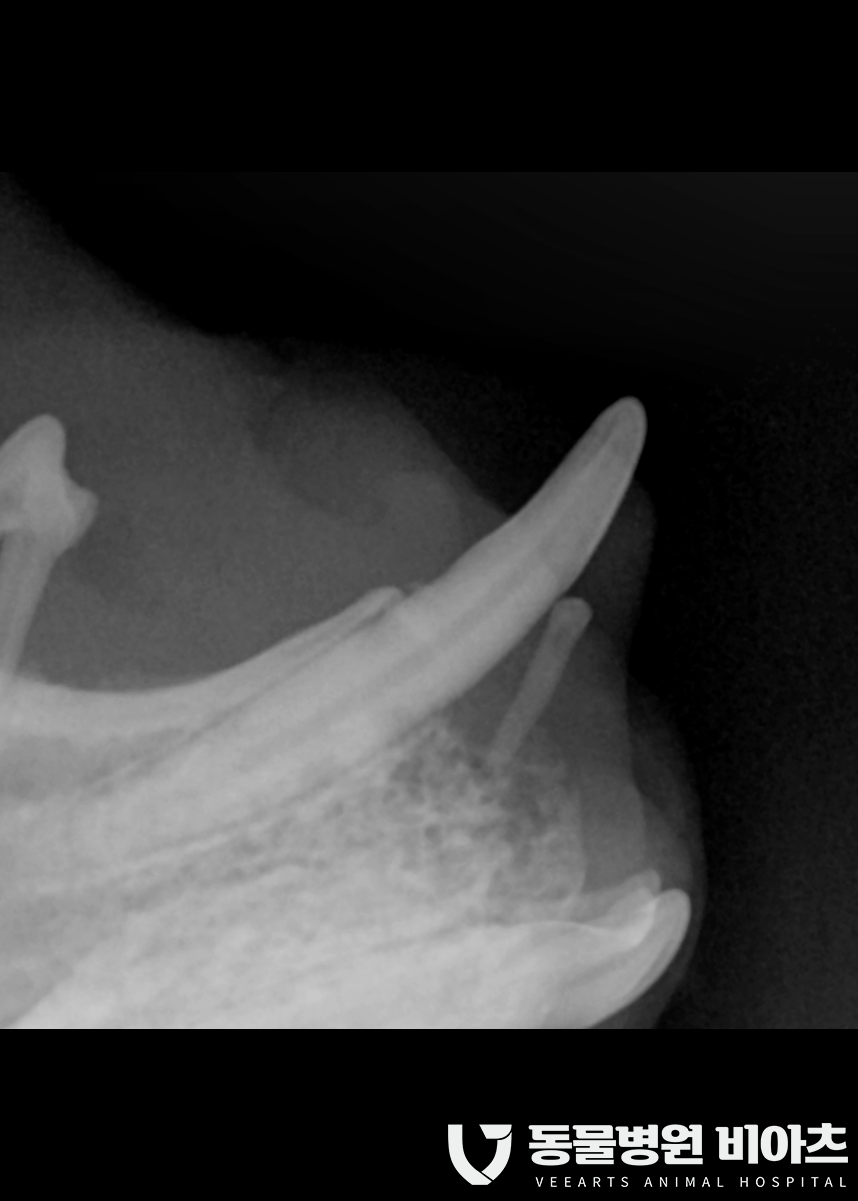

수술 전 치과 엑스레이를 통해

최소 10컷 이상의 촬영을 합니다.

치과 엑스레이는 보통 발치 전 발치 후

모두 찍습니다.

엑스레이 촬영을 통해 뿌리까지 완벽히 제거가

되었는지 확인을 해야 하기 때문입니다.

그냥 사진만 봐도

상태가..

많이 안 좋습니다..